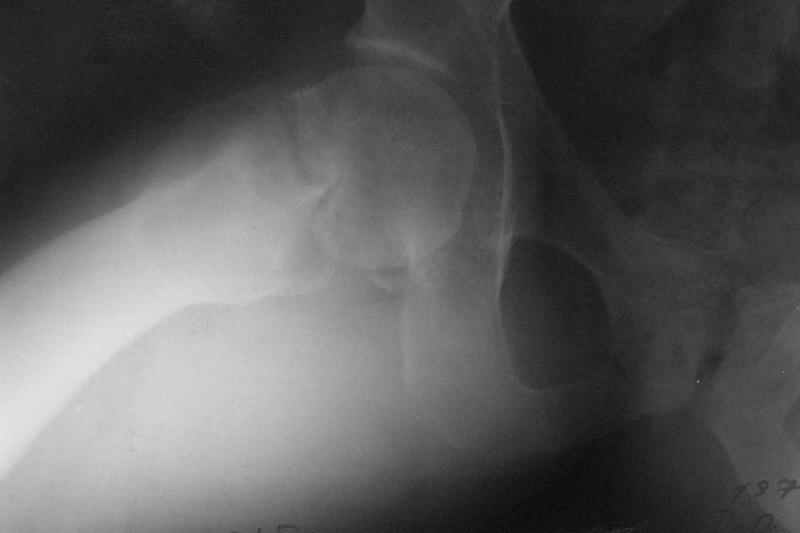

Однако на сегодняшнем снимке обнаружился перелом шейки бедра. Больной уже ходитс частичной нагрузкой. Учитывая срок и картину на снимке, что предпринять? У нас предложены варианты 1)не оперировать, 2)закрыто 2 спонгиозных винта, 3)вальгизирующая остеотомия. Эндопротез как-то даже в список включать пока не хочется. Какие есть соображения? Что из перечисленного или что-то другое выбрать и почему? Заранее спасибо.

Dear colleagues,A male 31 years old treated elsewhere after not severe pelvic fracture, was managed non operatively. So the injury looked as a reason of his inability to elevate the leg. However at the recent x-rays the neck fractire was found. The patient already has been walking with partial weight-bearing.Looking at the x-rays and the time since the injury, what is the optimal treatment for now? We discussed 1)leave as is, 2)2 cancellows screws as is, 3)valgus osteotomy. Total hip replacement looks unnecessary yet.What is your opinion? Which option from the listed or something else should be preferred and why?THX in advance.

Так его видно на фасном снимке.

Есть обзорный снимок таза, но не под рукой.

При явно выраженном варусе и флексионных состояниях после сросшихся переломов шейки бедра у молодых рекомендуется реконструктивная операция по исправлению варуса для предотвращения раннего деформирующего артроза, приводящего в результате переднего импинжмента, как показано на снимке.

Межвертельная вальгусная остеотомия представляет наименьший риск среди всех реконструктивных операции в проксимальной части бедра, создавая наилучшие биомеханические условия (увеличивается сила абдукторов, увеличивается сила суставной реакции, уменьшение рычага моментов абдукторов и уменьшение скольжения) и при меньшем риске повреждения кровоснабжения головки, где обычно в 90% случаях достигается отличный результат при применении метода для лечения ложных суставов шейки бедра.

case provided s/p failed fixation